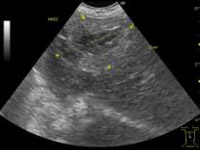

(腸管の肥厚、層構造不明瞭)

猫で最もよく見られるのが、消化器型です。高齢猫(10歳前後)が多く、胃腸・腸間膜リンパ・肝臓などに病変を形成するため、食欲不振、体重減少、嘔吐、下痢などを主訴に来院されます。低悪性度(Low-grade)のタイプも多く見られるため、診断には注意が必要です。

胸部レントゲン検査により縦隔の腫瘤や胸水の有無を確認します(縦隔型)。腹部レントゲンにより腹部臓器の大きさや位置を確認します(消化器型、多中心型、腎臓型)。超音波検査は、腹部臓器を

詳細に検査できます。